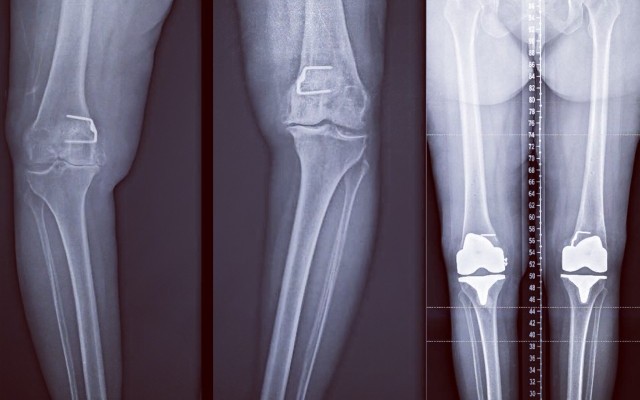

Posted in Dr Kaushik Hazratwala Blogs on Wednesday, 19 July 2017 by Kaushik Hazratwala

With the invent of new surgical techniques and instruments Knee Replacements can now be performed almost like Resurfacing. Taking as little bone as possible and resurfacing it with the equal amount of metal and plastic. Total Knee Replacement vs resurfacing The attached picture is from a knee arthroplasty I performed today. This is the actual picture of the bone cuts I performed on the...Baker's Cyst of The Knee